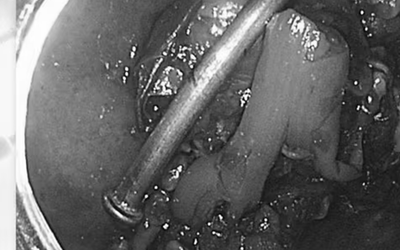

Con trai 8 tuổi nuốt phải dị vật nguy hiểm, người mẹ hốt hoảng đưa con đi cấp cứu. Ê-kíp bác sĩ "thót tim" phát hiện chiếc đinh nhọn kẹt ở tá tràng, suýt gây thủng ruột, viêm phúc mạc đe dọa tính mạng.